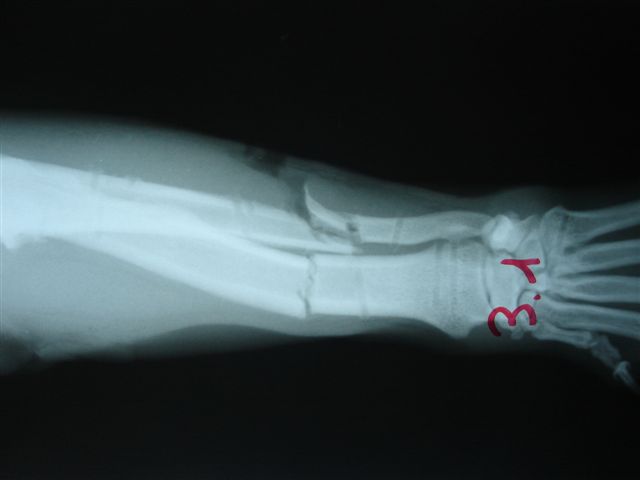

Fijación Externa en IVOT

Fijación Externa

IX CURSO BASICO DE FIJACION EXTERNA.

Casos prácticos alumnos.